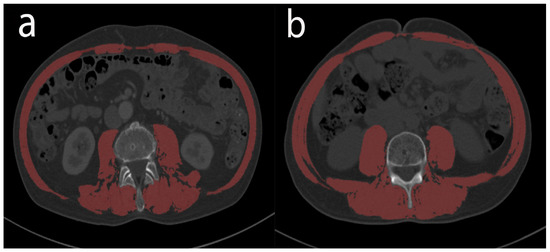

2.4. Nutritional and Inflammation Assessment